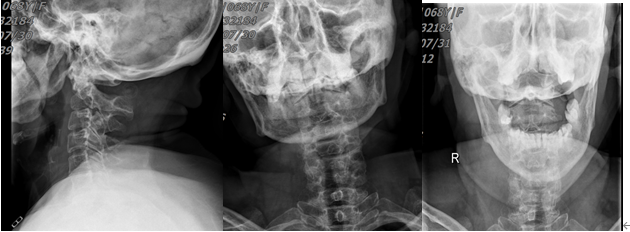

68歲的朱大媽騎電動車外出,不慎摔倒傷及頭頸部,求診漳州市中醫(yī)院骨傷科,行頸椎X線、CT、MRI檢查結(jié)果為:齒狀突骨折伴寰樞椎脫位。該部位的骨折伴脫位對于任何年齡段的患者都是非常危險(xiǎn)的,手術(shù)難度和風(fēng)險(xiǎn)非常高。寰樞椎釘棒內(nèi)固定融合術(shù)是治療此類疾病的最佳方案之一,但對手術(shù)團(tuán)隊(duì)醫(yī)護(hù)人員的要求極高。

圖一:頸椎齒狀突骨折、骨折移位伴寰樞椎脫位

圖二:頸椎齒狀突骨折,骨折線前下往后上,屬于IIC型